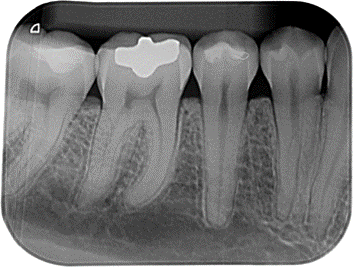

Radiografía periapical

La radiografía periapical digital forma parte de las radiografías intraorales, es una técnica radiográfica que permite al odontólogo obtener imágenes intraorales de alta resolución que sirve para explorar la pieza dentaria de corona a raíz junto con sus estructuras adyacentes.

Este tipo de radiografías se realizan habitualmente en la especialidad de Endodoncia para controlar y verificar el proceso de un tratamiento de conductos, antes, durante y después del tratamiento.

Dentro de la especialidad de periodoncia, en caso de sospecha de alguna posible lesión a nivel de la raíz o alrededor de la pieza dentaria. Se puede llegar a observar si hay pérdida ósea, bolsas periodontales, cálculo entre las piezas dentarias o bajo la encía y quistes periapicales.

También se llega a utilizar para el diagnóstico de caries de esta manera nos ayuda a determinar el grado de afectación si es superficial (de esmalte), o profunda (de dentina), también en caso de caries interproximal.

Este tipo de radiografía se realiza mediante una pequeña placa radiográfica que se introduce dentro de la boca a la altura de la pieza de interés, esta se impresiona a través de un aparato de rayos x externo el cual genera una imagen digital que se transmite a una pantalla.